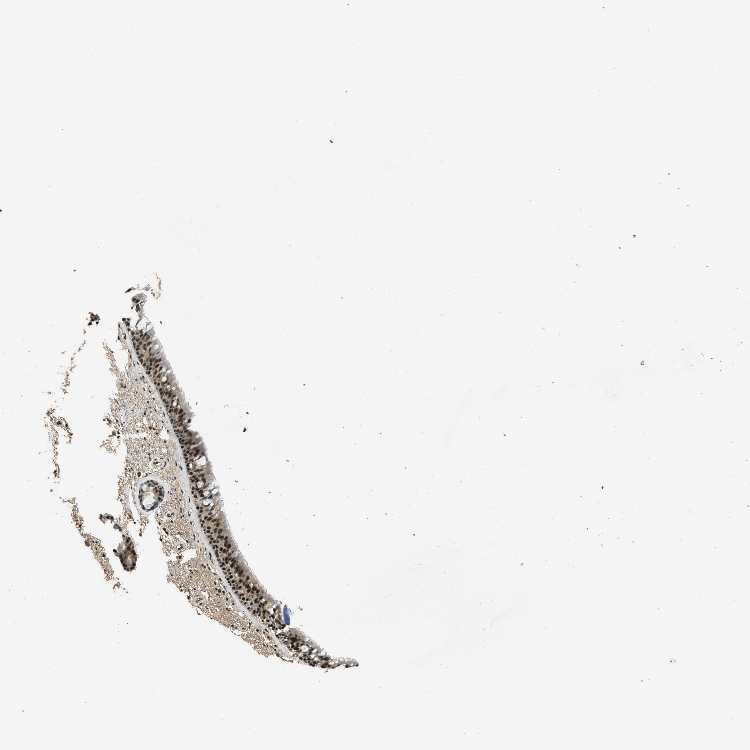

BRONCHUS - Antibody stainingi

Antibody staining in the annotated cell types in the current human tissue is reported as not detected, low, medium, or high, based on conventional immunohistochemistry profiling in selected tissues. This score is based on the combination of the staining intensity and fraction of stained cells.

Each image is clickable and will lead to virtual microscopy that enables deeper exploration of all samples and also displays staining intensity scores, fraction scores and subcellular localization as well as patient and tissue information for each sample.

Antibody CAB017486

Respiratory epithelial cells High